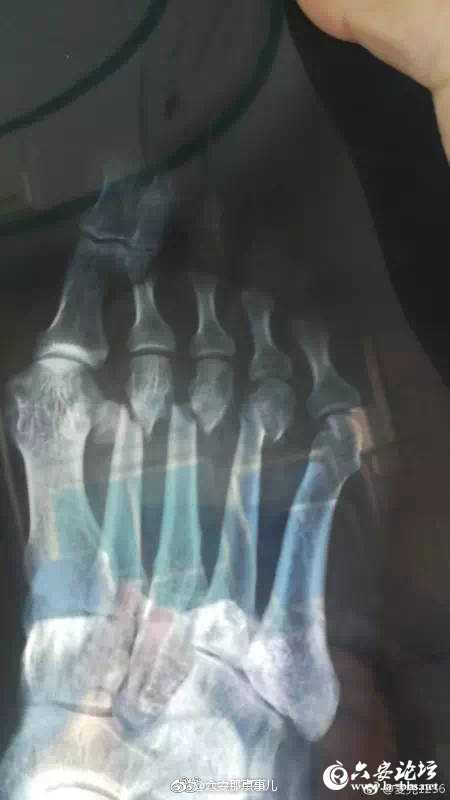

网友爆料:在金寨江店金江新城小区散步时,路面一处井盖破损,周围也没有任何警示标志,不慎在此处跌倒受伤,医生诊断其三根脚趾骨严重错位断裂。在此期间医疗费用更是多达两万余元!维权之路艰辛又漫长。小编发现,该网友在书记信箱里也发表过意见,希望能得到妥善处理。事儿妈要提醒下大家:

六安

城区也有很多破损井盖,都存在很大的安全隐患!走路时,要多注意!